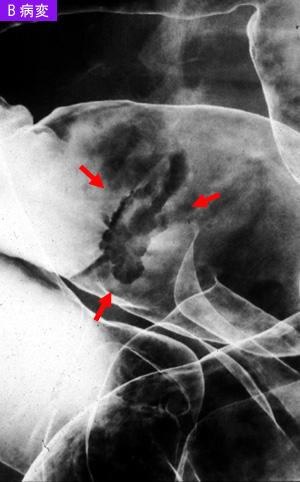

疾患(病理主体)の分類悪性上皮性腫瘍/腺癌

部位(臓器別)大腸/S状

検査方法X-P

腫瘍の肉眼分類0型(表在型)/IIa型(IIa+IIc)

病変の最大径(ミリ)15〜19

腫瘍の深達度sm

多発腫瘍(同一臓器)有(同時性)